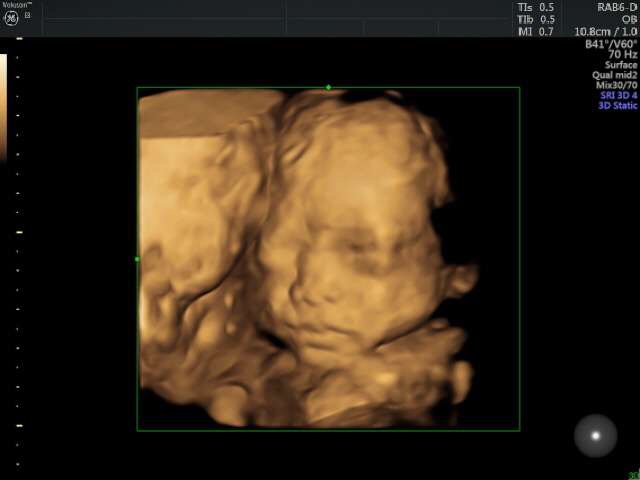

首先,四维彩超可以更加清晰地观察胎儿的发育情况,及时发现一些异常情况。通过四维彩超可以看到胎儿的面部特征、四肢动作等,有助于医生判断胎儿是否有先天性畸形。这对于早期发现并治疗胎儿异常是非常有帮助的。

其次,四维彩超可以帮助医生检查胎儿的器官是否正常发育。通过四维彩超可以看到胎儿心脏、脑部、肾脏等器官的情况,及时发现问题并采取相应措施。这对于预防和治疗胎儿畸形起到了积极的作用。